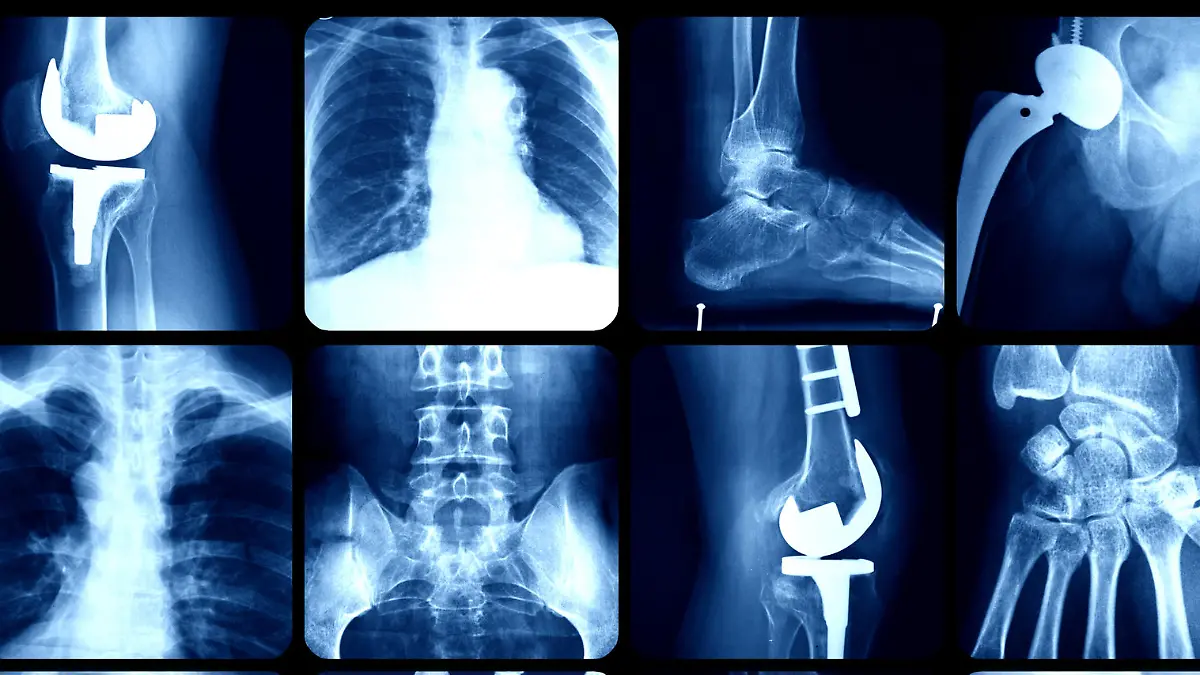

Ein Neugeborenes verfügt über 350 Knochen. Im Erwachsenenalter reduziert sich diese Zahl, da viele miteinander verwachsen. Mit seinen 208 bis 212 Knochen, vom Schädel bis zum Zeh, verfügt der Körper über ein solides und verlässliches Grundgerüst. Knochen oder auch Knochengewebe ist eine sehr harte Form von Stütz- und Bindegewebe. Die Summe aller Knochen bildet das Skelett. Knochen unterscheiden sich in Form und Funktion stark. Angefangen beim nur wenige Millimeter großen Gehörknöchelchen bis zum längsten Knochen, dem Oberschenkelknochen, hat jeder seine Aufgabe. Der Schädel dient beispielsweise als Schutz für das Gehirn. Ebenso imposant ist die Schutzfunktion des Brustkorbs. Dieser birgt Herz, Lunge und weitere lebenswichtige Organe. Das Becken schützt die sensiblen Fortpflanzungsorgane.

Man unterscheidet hauptsächlich zwischen drei Arten von Knochen: Röhrenknochen, platte Knochen und kurze Knochen. Einige unserer Knochen sind hohl und mit Knochenmark gefüllt. Hier finden lebenswichtige Prozesse wie die Blutbildung, also die Herstellung der roten Blutkörperchen, statt. Neben der ebenso wichtigen Schutzfunktion haben Knochen viele weitere Funktionen. Sie speichern zum Beispiel unverzichtbare Mineralsalze wie Magnesium, Calcium und Phosphor. Darüber hinaus stützen sie das Skelett und ermöglichen im Zusammenspiel mit Gelenken, Sehnen und Bändern die Bewegung. Knochen sind außerdem der härteste Bestandteil des Körpers, sieht man von den Zähnen ab.

Die bekannteste Knochenkrankheit ist die Fraktur, das heißt ein Knochenbruch. Es kann fast jeden Knochen treffen, vor allem Arme und Beine. Hierbei handelt es sich um eine enorme Verletzung des Skeletts, die je nach betroffenem Areal das Leben sehr einschränken kann. Weitere typische pathologische Veränderungen sind Osteoporose, Knochenkrebs, die Glasknochenkrankheit und der Bandscheibenvorfall. Letztgenannte Problematik beschreibt eine Erkrankung der Wirbelsäule, nämlich den Durchbruch des Gallertkerns einer oder mehrerer der 23 Bandscheiben. Die Folge sind Rückenschmerzen, welche je nach betroffener Zone sehr schmerzhaft werden können. Eine Behandlung ist dann unverzichtbar, da es sich hier keinesfalls um einen sogenannten Hexenschuss handelt.